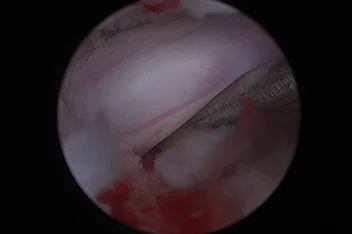

부울경 최초 ‘양방향 척추내시경’ 도입

정밀하고 덜 아픈 척추 수술의 새로운 패러다임

양방향 척추 내시경 BESS, Biportal Endoscopic Spine Surgery

기존의 단일 포털 내시경(uniportal endoscopy)의 한계를 극복한

정밀한 양손 작업이 가능한 최소침습 기술입니다.

리본동물의료센터 2025년 1월부터 부울경 최초로 양방향 척추 내시경을 도입해왔으며, 영남권 최다 임상 CASE를 축적하고 있습니다.

양방형 척추 내시경 수술의 핵심 장점

• 정밀한 수술 조작

• 근육 인대 손상 최소화

• 절개 최소화

• 빠른 회복과 낮은 통증

• 고배율 직시 시야 확보

양방형 척추 내시경 수술 전

양방형 척추 내시경 수술 후

양방형 척추 내시경 모식도